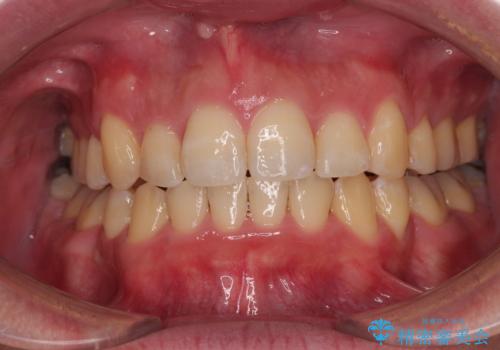

上下前歯の前後差が非常に大きく、3年以上の治療期間が予想されましたが、無事に3年間ちょうどで仕上げることができました。